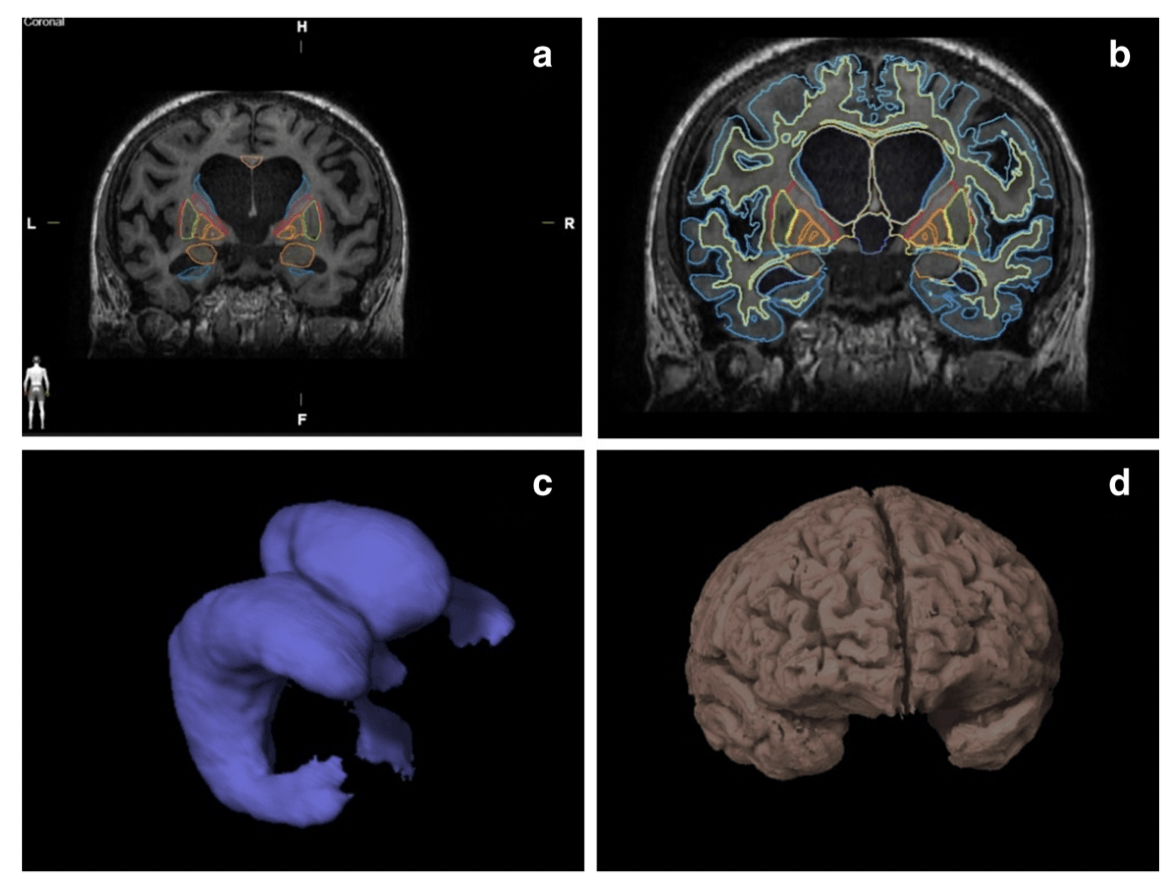

All structures relevant to NPH diagnosis were automatically segmented using Anatomical Mapping 1.1 as a part of Brainlab Elements software. We have successfully measured volumes of both white and grey matter, internal and external capsule, corpus callosum, hippocampus, amygdala, caudate nucleus, putamen, internal and external globus pallidus, thalamus, periaqueductal grey and three ventrucles. The fourth ventricle was manually removed from the ventricular system measurement in the level of the cerebral aqueduct because its volume is not related to NPH diagnosis. The results were subsequently tested using ANOVA analysis. Significant differences in the volumes of the corpus callosum, left hippocampus, internal globus pallidus, grey and white matter and ventricular volumes were observed between NPH group and healthy controls. However, the differences between NPH and non-NPH groups were non-significant. Three months after, VP shunt insertion decreased ventricular volume was the only clearly significant result (p value 0.0001).